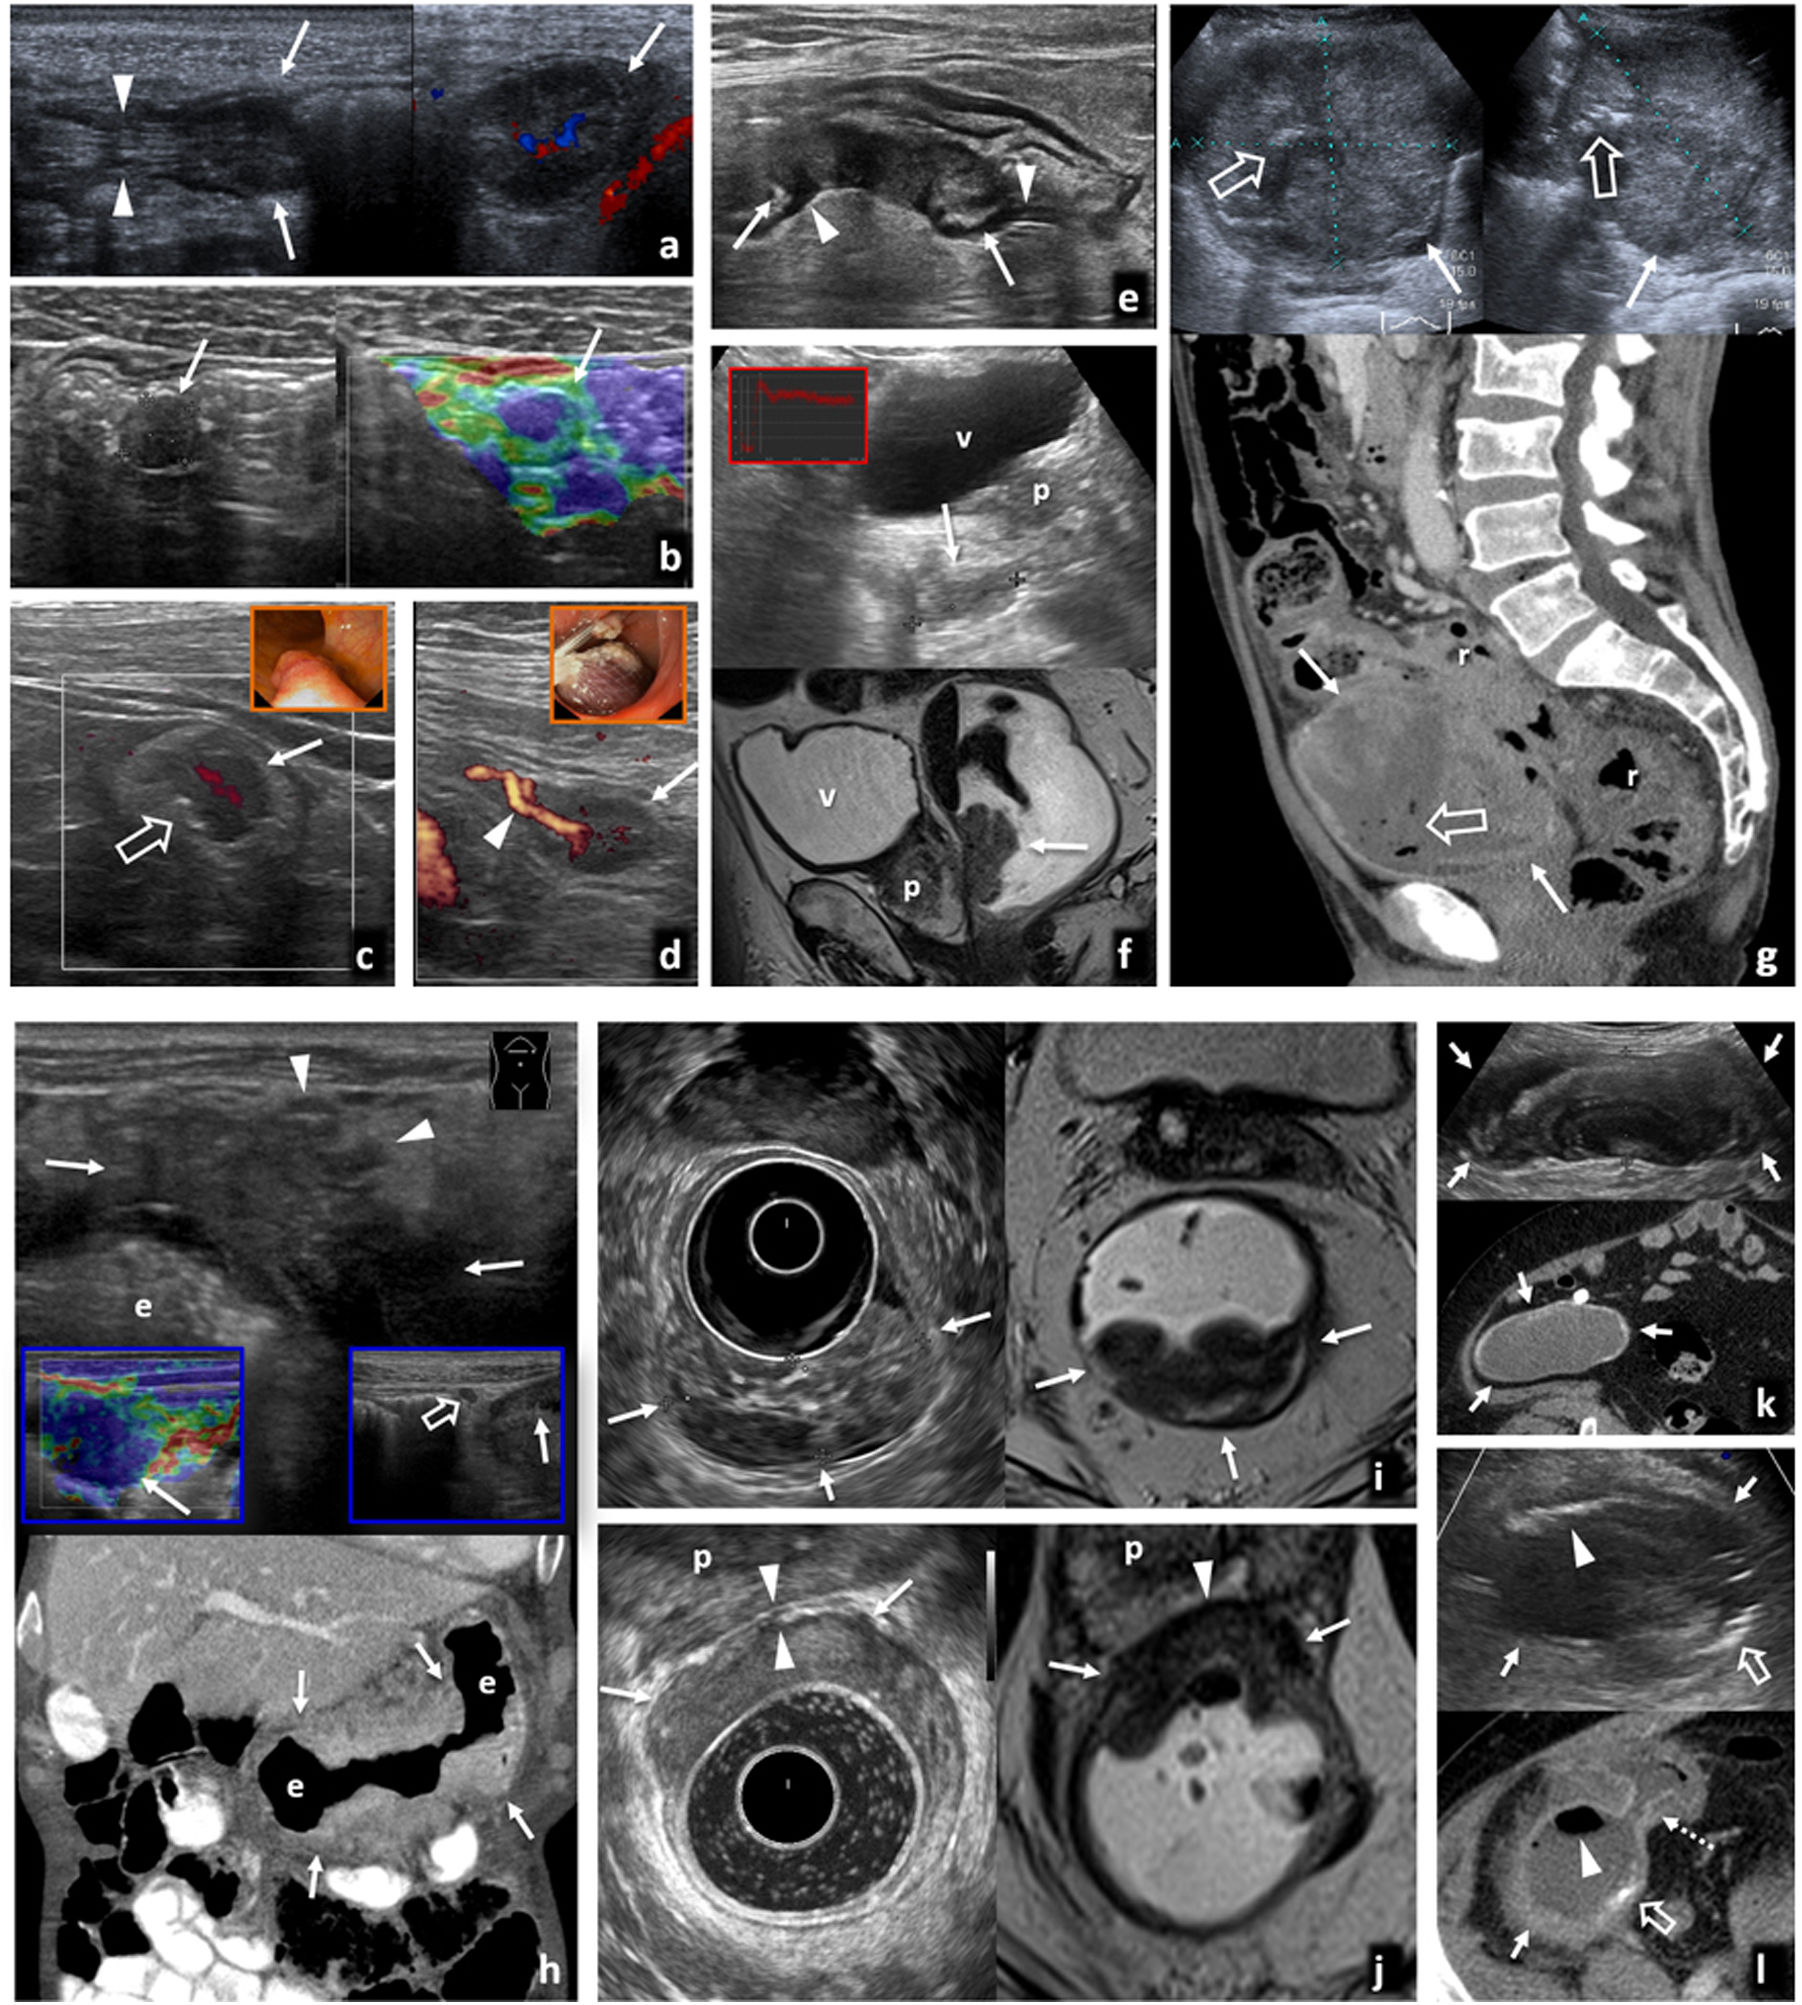

Afectación infecciosa del íleon distal. Primer caso de paciente joven con dolor abdominal y diarrea que consulta en el servicio de urgencias. Se realiza ecografía para filiar el origen del cuadro. Presentamos imágenes en corte longitudinal (A y B) del íleon terminal, objetivando un engrosamiento de la pared que conserva la estratificación de sus capas, afectando a la capa mucosa (cabezas de flecha) y submucosa (*) y respetando la capa muscular (flechas finas), característico de las enteritis infecciosas frente a otras causas de afectación intestinal. El estudio mediante Doppler color muestra un aumento de la vascularización secundaria al cuadro infeccioso (C). Se acompaña de tumefacción e hiperecogenicidad de la grasa mesentérica adyacente (+) y un ganglio ileocólico aumentado de tamaño de naturaleza reactiva (flecha gruesa). El cultivo de heces resultó positivo para Yersinia enterocolitica. Tras tratamiento antibiótico y sintomático, la paciente mejoró progresivamente hasta al alta. Segundo caso de paciente de 18 años, que acude al servicio de urgencias por febrícula y dolor abdominal en fosa iliaca derecha de horas de evolución. En la valoración inicial se realiza ecografía con la sospecha de apendicitis aguda, en la que se aprecia un engrosamiento de la pared de íleon terminal que se extiende al ciego (D) y un apéndice ileocecal de calibre normal (E), que orienta a cuadro infeccioso, descartando la sospecha diagnóstica que motivó la petición. A las 24 horas, se solicita una tomografía computarizada abdominal. Mostramos una imagen de reconstrucción coronal del estudio en la zona de interés (F), que muestra los mismos hallazgos. Dada la persistencia de la clínica, se decide intervenir quirúrgicamente a la paciente, practicando una resección ileocólica con el resultado histológico de enterocolitis supurada con apéndice normal. No pudo determinarse en el estudio microbiológico el agente infeccioso que originó el cuadro.

Afectación infecciosa del peritoneo. A-D) Hallazgos característicos de peritonitis tuberculosa en varios pacientes. Adenopatías mesentéricas (A) con centro hipoecoico por presencia de necrosis (*), afectación esplénica (B) con absceso en polo inferior del bazo (cabeza de flecha) y ascitis (C) con punteado ecogénico por material denso. Un dato significativo es el engrosamiento del epiplón mayor (flechas gruesas), que se aprecia con detalle en la ecografía (D), y se correlaciona con la imagen tomográfica mostrada en la esquina inferior izquierda. Plantea el diagnóstico diferencial con infiltración tumoral, por lo que precisa habitualmente de estudio histológico tras la obtención de una muestra que puede ser guiada ecográficamente como se aprecia en la imagen de la esquina inferior derecha. E-G) Peritonitis de otro origen. En el primer caso (E), paciente con cuadro de apendicitis aguda que se acompaña de discreta cantidad de líquido libre entre asas, con punteado ecogénico (+) y engrosamiento lineal del peritoneo parietal (flecha fina) que indica la presencia de peritonitis focal asociada. El segundo caso, peritonitis parasitaria en paciente con quiste hidatídico hepático (F) con membranas plegadas y presencia de líquido perihepático (G) que indica complicación del mismo con rotura y diseminación peritoneal del contenido.

Pólipos y carcinomas. A) Pólipo adenomatoso hipoecogénico de 13 mm (flechas) en la luz del colon transverso, con un pedículo que sigue la estructura en capas de la pared (cabezas de flecha) y flujo demostrado en Doppler (derecha). Hallazgo incidental en varón de 77 años. B) Pólipo adenomatoso hipoecogénico (flechas) en el colon sigmoide, hallazgo incidental en varón de 44 años. La estabilidad de la imagen en el tiempo y la rigidez tisular, con tonos azules en la imagen de elastografía cualitativa de presión o strain (derecha), confirman el hallazgo. C) Carcinoma Hagitt 1 sobre pólipo adenomatoso hipoecogénico de 15 mm (flecha) en la luz del colon izquierdo distal, con un vaso en su interior en Doppler y una pequeña ulceración superficial (flecha hueca). Hallazgo incidental en ecografía por ateromatosis en varón de 67 años. En el recuadro, imagen de colonoscopia previa a resección. D) Carcinoma Hagitt 1 sobre pólipo adenomatoso hipoecogénico de 20 mm (flecha) en la luz del colon sigmoide, con un vaso en su pedículo en Doppler (cabeza de flecha). Hallazgo incidental en estudio por molestias abdominales inespecíficas en mujer de 78 años. En el recuadro, imagen durante la resección endoscópica. E) Adenocarcinoma infiltrante de colon sigmoide T2 N0 M0 en ecografía por anemia en varón pluripatológico de 85 años. Engrosamiento hipoecogénico infiltrante con retracción de la pared posterior del colon (flechas), sin rebasar la capa muscular propia hipoecogénica (cabezas de flecha). La ecografía es más precisa que la tomografía computarizada (TC) (no mostrada) en la estadificación locorregional en este caso, permitiendo un abordaje quirúrgico laparoscópico rápido y limitado en un paciente clínicamente complejo. F) Carcinoma polipoideo en recto inferior, hallazgo ecográfico empleando la vejiga (v) como ventana acústica. Lesión nodular hipoecogénica (flechas) de 33 mm. En el recuadro, curva intensidad/tiempo de ecografía con contraste para confirmar el hallazgo (vídeo 1). p: próstata. Imagen inferior: correlación en resonancia magnética (RM) sagital potenciada en T2 con gel endorrectal para estadificación locorregional. G) Carcinoma de transición colorrectal como masa exofítica ulcerada y necrótica que simula GIST. imagen superior: ecografía, sección transversal (izquierda) y longitudinal (derecha) sobre hipogastrio. Masa hipoecogénica heterogénea (flechas) por necrosis, con focos de gas (flechas huecas) por ulceración. Imagen inferior: TC sagital. La masa contacta con la cara anterior del recto-sigma (r). Se sospechó GIST, pero correspondió a un adenocarcinoma con un patrón infrecuente de presentación. H) Adenocarcinoma gástrico T4a N2 M0. Imagen superior: ecografía por síndrome constitucional en varón de 83 años. Engrosamiento hipoecogénico marcado e irregular de la pared del estómago (e: luz gástrica), con ulceraciones (no mostrado) y clara extensión nodular a la grasa del ligamento gastrocólico (cabezas de flecha). La elastografía (recuadro inferior izquierdo) muestra marcada rigidez tisular. Se ven también adenopatías regionales (flecha hueca en recuadro inferior derecho). Imagen inferior: TC coronal en fase portal. La gran delgadez del paciente hace que la estadificación sea menos precisa que con ecografía. I) Adenocarcinoma rectal T1 sobre pólipo velloso (flechas) en varón de 67 años. La ecografía endorrectal (izquierda) muestra una lesión polipoidea de ecogenicidad intermedia, definiendo con más precisión que la RM (derecha: T2 transversal con gel endorrectal) la indemnidad de la capa muscular propia (hipoecogénica), permitiendo la resección transanal. J) Adenocarcinoma de recto inferior T3a superficial en varón de 72 años. La ecografía endorrectal (izquierda) muestra con precisión un engrosamiento hipoecogénico excéntrico en la cara anterior del recto inferior, que transgrede la capa muscular propia hipoecogénica con nodulaciones superficiales (flechas), confirmando extensión T3 superficial. Se demuestra la preservación de un plano graso (cabezas de flecha) con la próstata (p). La RM transversal T2 (derecha) plantea dudas en este caso desde T2 hasta T4b por infiltración prostática. K) Mucocele apendicular. Imagen superior: hallazgo ecográfico incidental en mujer de 77 años con colecistitis aguda litiásica. Masa ovoidea con estructura interna en capas con ecogenicidades alternantes (patrón “en capas de cebolla” característico) en fosa iliaca derecha (flechas). Imagen inferior: la TC axial muestra finas calcificaciones parietales, pero no es capaz de demostrar la estructura mucinosa de la lesión quística con la precisión de la ecografía. L) Mucocele apendicular sobreinfectado y comunicado con el ciego. Imagen superior: ecografía en varón de 62 años con dolor abdominal y fiebre. Masa quística heterogénea en fosa iliaca derecha (flecha), con focos ecogénicos que representan gas (cabeza de flecha) y calcificaciones parietales (flecha hueca). Imagen inferior: la TC demuestra además la comunicación del mucocele con la luz del ciego (flecha discontinua).

Tumores neuroendocrinos. A) Tumor carcinoide de íleon terminal. Mujer de 62 años con vómitos y dolor abdominal. Antecedente de macroadenoma hipofisario intervenido. Imagen superior: ecografía. Imagen inferior: tomografía computarizada (TC) coronal. Lesión nodular hipoecogénica con abundante vascularización en Doppler y TC (flechas), en el ángulo interno de tramo plegado de íleon distal (+), con peristaltismo ineficaz a tiempo real (vídeo 2). Además, adenopatías hipoecogénicas y vascularizadas (cabezas de flecha) en meso regional tumefacto y ecogénico (m). Se diagnostica MEN-1. En el recuadro: implante endometriósico (*) en íleon terminal (+) en otra paciente, como nódulo hipoecogénico que infiltra la serosa, retrayendo el asa y respetando las capas profundas, que muestra hallazgos similares y con el que hay que establecer diagnóstico diferencial (no vascularizado y sin afectación adenopática en este caso). B) Carcinoide ileal solo manifestado como masa mesentérica. Imagen superior: biopsia percutánea (flechas huecas) guiada ecográficamente de nódulo mesentérico hipoecogénico (flecha), que demostró metástasis ganglionar de tumor neuroendocrino. Imagen inferior: TC coronal con contraste oral e intravenoso. Nódulos adenopáticos mesentéricos (flechas). En la cirugía se identificó un carcinoide milimétrico intestinal primario y retrospectivamente podría corresponder al pequeño defecto de repleción indicado por la cabeza de flecha. C) Carcinoides yeyunales múltiples y metástasis ganglionares mesentéricas. Mujer de 71 años con molestias abdominales inespecíficas. Imágenes superiores: ecografías. Centrales e inferiores: imágenes axiales de entero-TC en dos planos diferentes. Se detectan hasta 5 tumores hipoecogénicos e hipervasculares (uno no mostrado) en tramos plegados de yeyuno (flechas), con un pequeño conglomerado adenopático también hipervascular e hipoecogénico en el meso tributario (cabezas de flecha). D) Síndrome de Zollinger-Ellison por tumor neuroendocrino de tipo II (gastrinoma) de tracto digestivo superior. Varón de 44 años con vómitos, diarrea y shock. Imagen izquierda: ecografía. Imagen derecha superior: TC axial. Abundante líquido en estómago (e), duodeno (d) y yeyuno proximal (no mostrado), con marcado engrosamiento de pliegues gástricos (cabezas de flecha). Medial al duodeno y posterior al páncreas se ve un nódulo hipervascular y levemente ecogénico (flechas) en el seno de una estructura ganglionar. Esta región está dentro del llamado “triángulo del gastrinoma”. Derecha centro: gammagrafía con octeótrida. Se confirma captación por parte del nódulo (flecha). También hay hipergastrininemia. Derecha inferior: pieza quirúrgica del gastrinoma (flechas) en el seno de un ganglio. E) Carcinoma neuroendocrino gástrico de tipo III. Varón de 59 años con síndrome constitucional. La ecografía muestra abundantes metástasis hepáticas (m) y, empleando el bazo (b) como ventana acústica, un tumor infiltrante en la curvatura mayor del estómago. Se sospechó un adenocarcinoma, pero la biopsia endoscópica demostró un carcinoma neuroendocrino. F) Tumor neuroendocrino rectal. Hallazgo en la colonoscopia por test de sangre oculta en heces positivo en varón de 62 años. Imagen superior: ecografía transrectal. Imagen inferior: RM T2 axial. Tumor de 7× 5 mm (flechas) con comportamiento hipoecogénico e hipointenso en T2, situado en la parte profunda de la capa submucosa del recto inferior, con moderada rigidez tisular en elastografía (recuadro central), con strain ratio de 10 con respecto a la pared rectal normal. Se realizó una resección endoscópica transanal.

Linfomas gastrointestinales. A) Linfoma difuso de células grandes de íleon terminal. Mujer de 36 años. Imagen izquierda: tomografía computarizada (TC) coronal con contraste oral e intravenoso. Imagen derecha: ecografía. Engrosamiento mural hipoecogénico e hipovascular marcado en un tramo largo de íleon distal (flechas) cuya luz se encuentra dilatada (*). Se acompaña de una masa mesentérica adyacente de ecogenicidad similar (cabezas de flecha), sobre la que se realizó BAG guiada ecográficamente (flechas huecas). B) Linfoma difuso de células grandes de yeyuno distal. Varón de 70 años. Imagen superior: TC coronal con contraste oral e intravenoso. Imagen inferior: ecografía. Engrosamiento mural hipoecogénico e hipovascular marcado en un tramo más corto de yeyuno distal (flechas), también con dilatación aneurismática (*) y una masa mesentérica adenopática acompañante (cabeza de flecha). El diagnóstico se consiguió con la biopsia percutánea del engrosamiento intestinal (no mostrado). C) Enfermedad inmunoproliferativa de intestino delgado (o “linfoma mediterráneo”, subtipo de linfoma extranodal de la zona marginal). Varón de 17 años con diarrea, fiebre y dolor abdominal. La ecografía muestra adenopatías mesentéricas homogéneas (cabezas de flecha), engrosamiento de pliegues de yeyuno proximal (flechas), con una invaginación larga de yeyuno (flechas discontinuas) con mesenterio en su interior (m), así como pequeñas lesiones focales hepáticas hipoecogénicas (flechas huecas). El diagnóstico se obtuvo con la biopsia de dos lesiones focales hepáticas (no mostrado). D) Linfoma T gástrico de alto grado asociado a enteropatía. Varón de 61 años con diagnóstico de enfermedad celiaca. Imagen superior: TC. Imagen inferior: BAG guiada ecográficamente. Engrosamiento circunferencial hipovascular e hipoecogénico (no mostrado) de antro gástrico (flechas), con múltiples lesiones focales hepáticas hipocaptantes (cabezas de flecha) y levemente hipoecogénicas. En la gastroscopia se ve una lesión antral ulcerada, pero las biopsias son repetidamente negativas. El diagnóstico se consigue con la biopsia percutánea de las lesiones hepáticas. E) Linfoma folicular de bajo grado de yeyuno proximal. Varón de 73 años. Imagen izquierda: TC axial (superior) y coronal MIP fino (inferior). Imagen derecha: ecografía, corte transversal (superior) y biopsia percutánea. Engrosamiento mural excéntrico de un tramo de yeyuno proximal (cabezas de flecha) con una gran masa mesentérica (flechas) que se extiende hasta el ángulo de Treitz (t), con escaso efecto de masa sobre los vasos mesentéricos a su través. a: aorta. Ecográficamente se define mejor la heterogeneidad de este conglomerado adenopático, lo que permite dirigir la biopsia percutánea a la parte más sólida de la masa mesentérica (flechas huecas). Persiste en remisión completa tras 3 años de iniciar la quimioterapia. F) Linfoma de Burkitt ileocecal. Mujer de 46 años. Imagen izquierda: ecografía. Imagen derecha: TC coronal. Engrosamiento mural importante, excéntrico, en la región ileocecal (flechas) sin estenosis de la luz (*) y con cierta sensación de preservación de la estructura ecográfica en capas a pesar de la magnitud del engrosamiento. Se acompaña de un conglomerado adenopático mesentérico (cabezas de flecha) que se define con más precisión en la ecografía, así como numerosas lesiones focales hepáticas (flechas discontinuas) y ascitis (+). Persiste en remisión completa tras 4 años de iniciar la quimioterapia. G) Linfoma de células del manto de alto grado con afectación de ángulo esplénico del colon. Mujer de 69 años. Imagen izquierda: TC coronal. Imagen derecha: ecografía. Gran masa que engloba el ángulo esplénico del colon (c) y se extiende hacia su meso (flechas). Se acompaña de afectación de íleon distal (i), vesícula (v) y útero (u) como engrosamiento visceral, así como adenopatías mesentéricas (cabezas de flecha), ascitis (+) y linfomatosis peritoneal (flechas discontinuas). El diagnóstico se obtuvo con biopsia percutánea ecodirigida de la masa del mesocolon (flechas huecas).